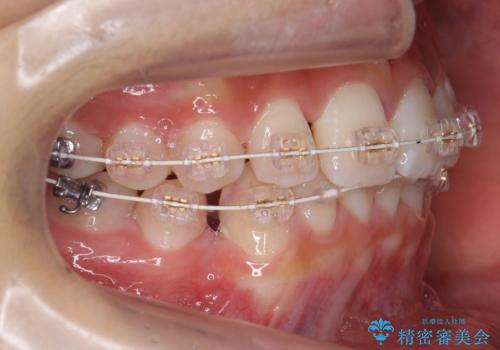

- 審美装置

- 1年7ヶ月

- 10-30回

犬歯の両側の歯に関しては移動することにより歯槽骨が順調に回復し、上顎洞底の形態にかかわらず歯根のパラレリングを行うことができた理由としては、年齢が10代前半と若かったからだと思います。

成人ですと、なかなかこういった柔軟な歯の移動は難しいことが多いです。

左上4−7については、近心傾斜をしていたため、右上3を抜かずに遠心に移動して非抜歯で治療を行う案も提案しましたが、抜歯を選択されました。結果的に深く埋まっていた右上犬歯を牽引せずにすみ、さらに歯根の向きも整えることができてよかったです。治療も比較的短期間で済みました。